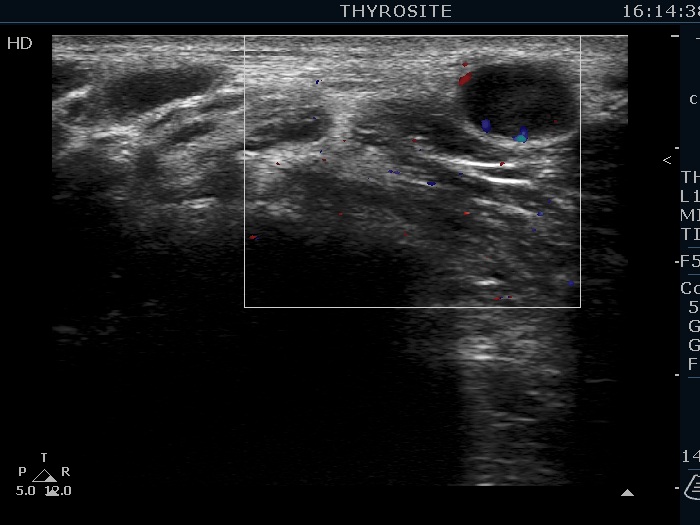

Lymph nodes - case 1131 (ultrasonographic picture 17)

Above and lateral to the left lobe, transverse scan, color Doppler mode. There are signs of vascularity.